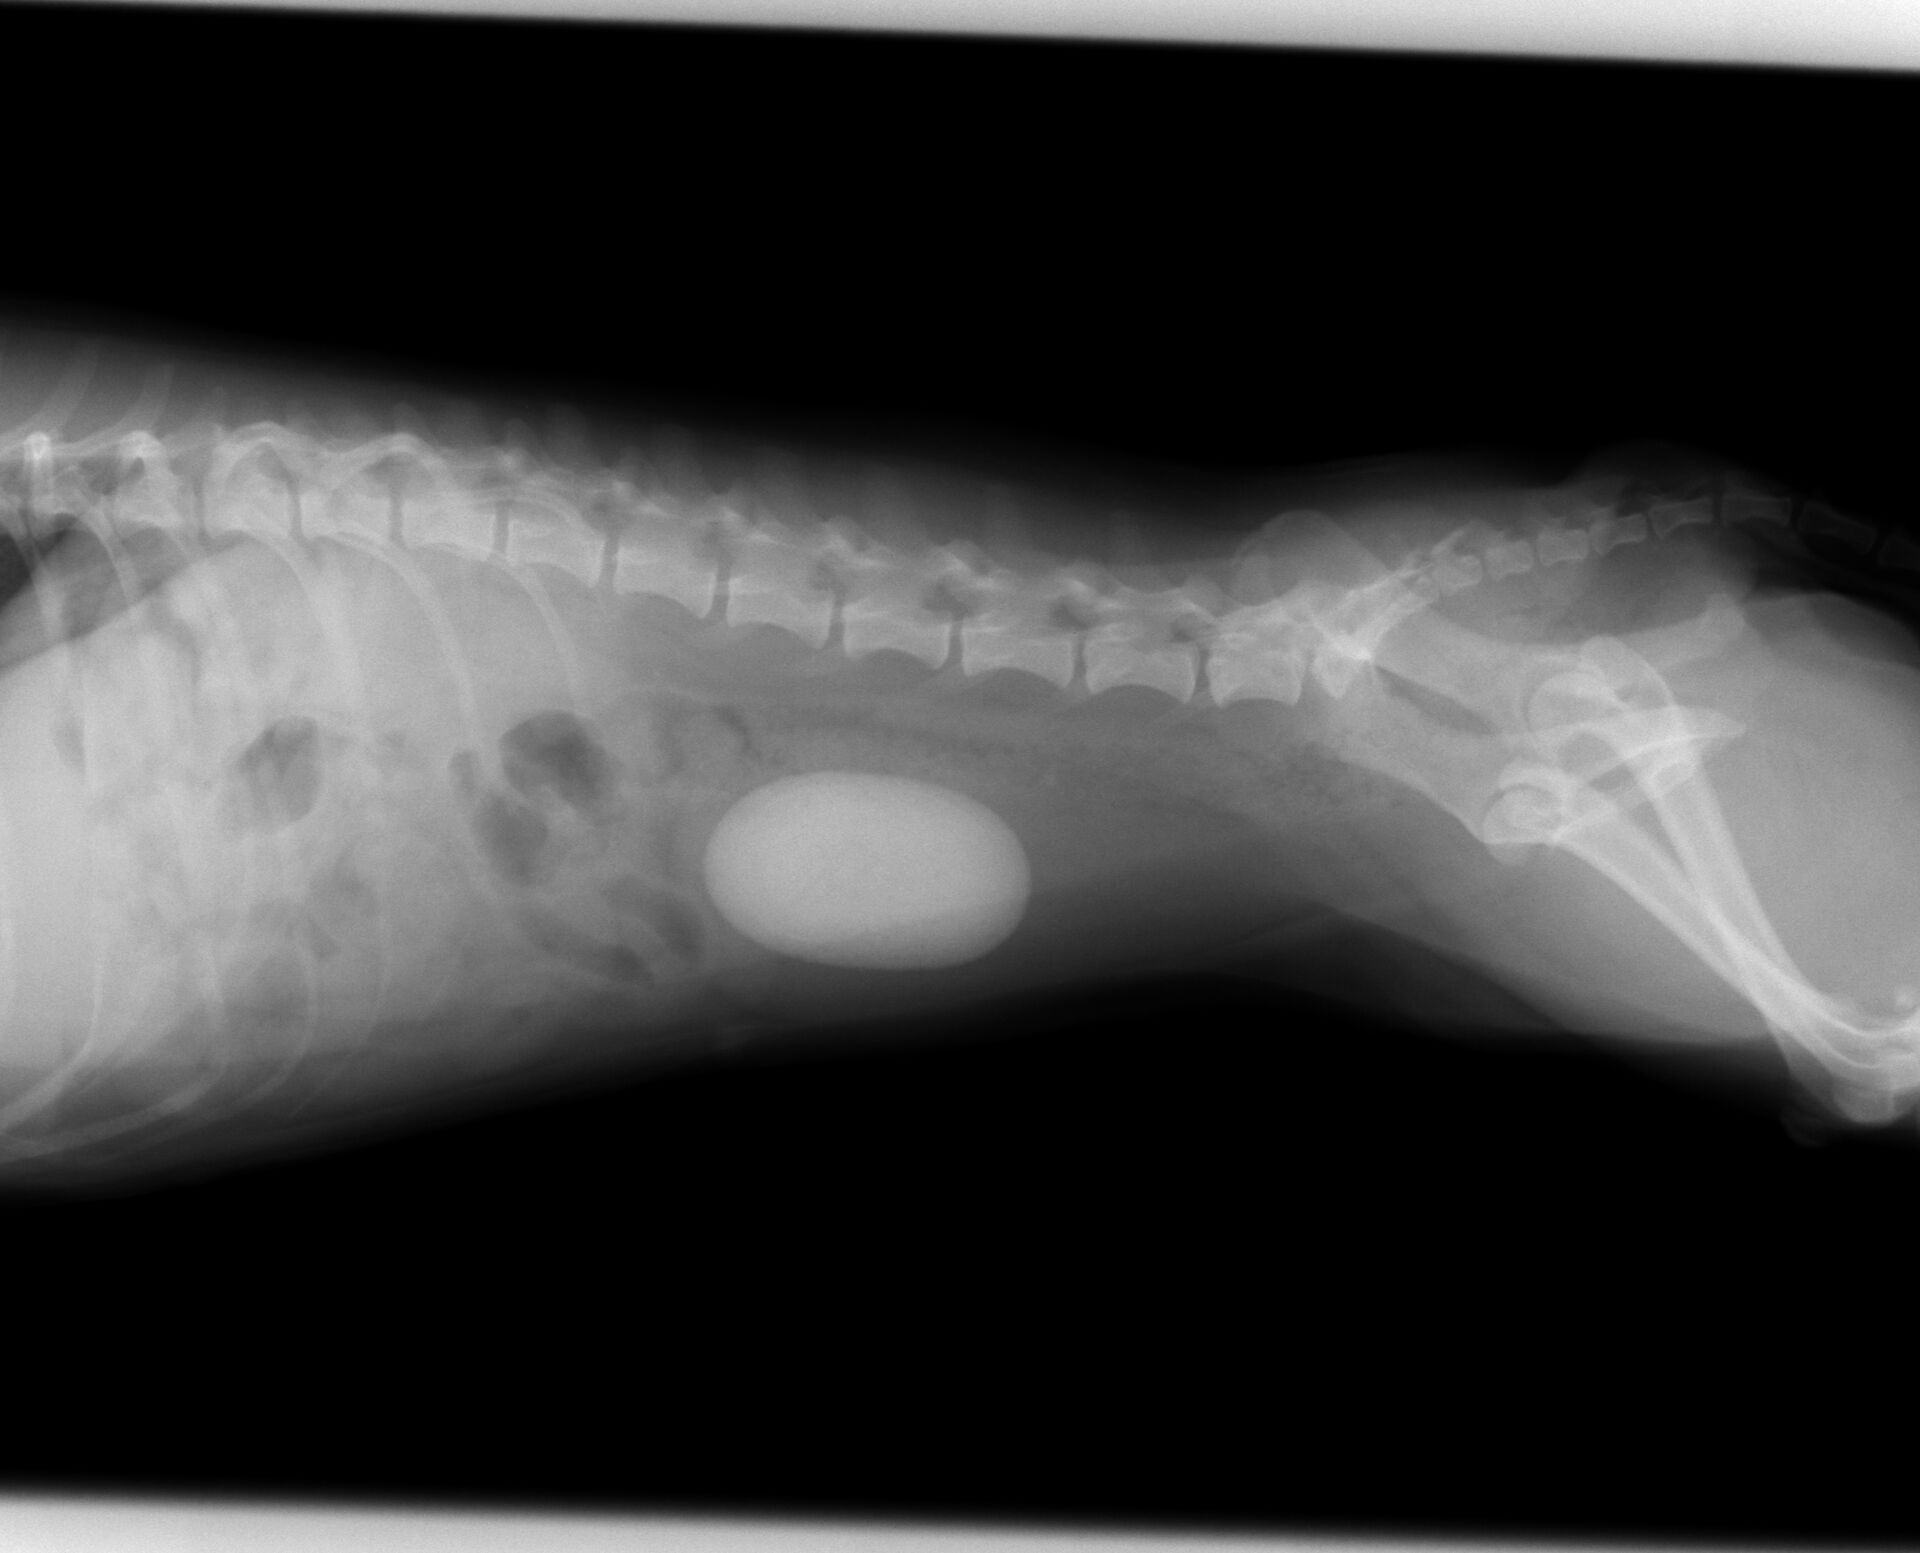

膀胱結石に間違いないと判断し、レントゲンを撮りました。

それが下の写真です。かなり大きな膀胱結石が存在していました。

ここまで大きくなってしまうと膀胱切開して取り出すしかありません。

手術が必要です。血液検査、心電図で問題がありませんでしたので、

次の日に手術を行いました。取り出した結石が下の写真です。